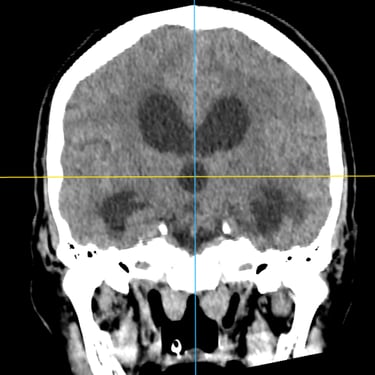

Hidrocefalia – Colocación de derivación ventriculoperitoneal (DVP).

La hidrocefalia es una condición neurológica causada por la acumulación anormal de líquido cefalorraquídeo dentro de los ventrículos cerebrales, lo que genera aumento de la presión intracraneal y deterioro neurológico progresivo. La colocación de una derivación ventrículoperitoneal (DVP) es el tratamiento quirúrgico más utilizado para controlar esta patología. Este sistema permite drenar el exceso de líquido desde el cerebro hacia la cavidad abdominal, donde se reabsorbe de manera segura. La intervención oportuna alivia los síntomas, previene daño cerebral y mejora la calidad de vida del paciente.